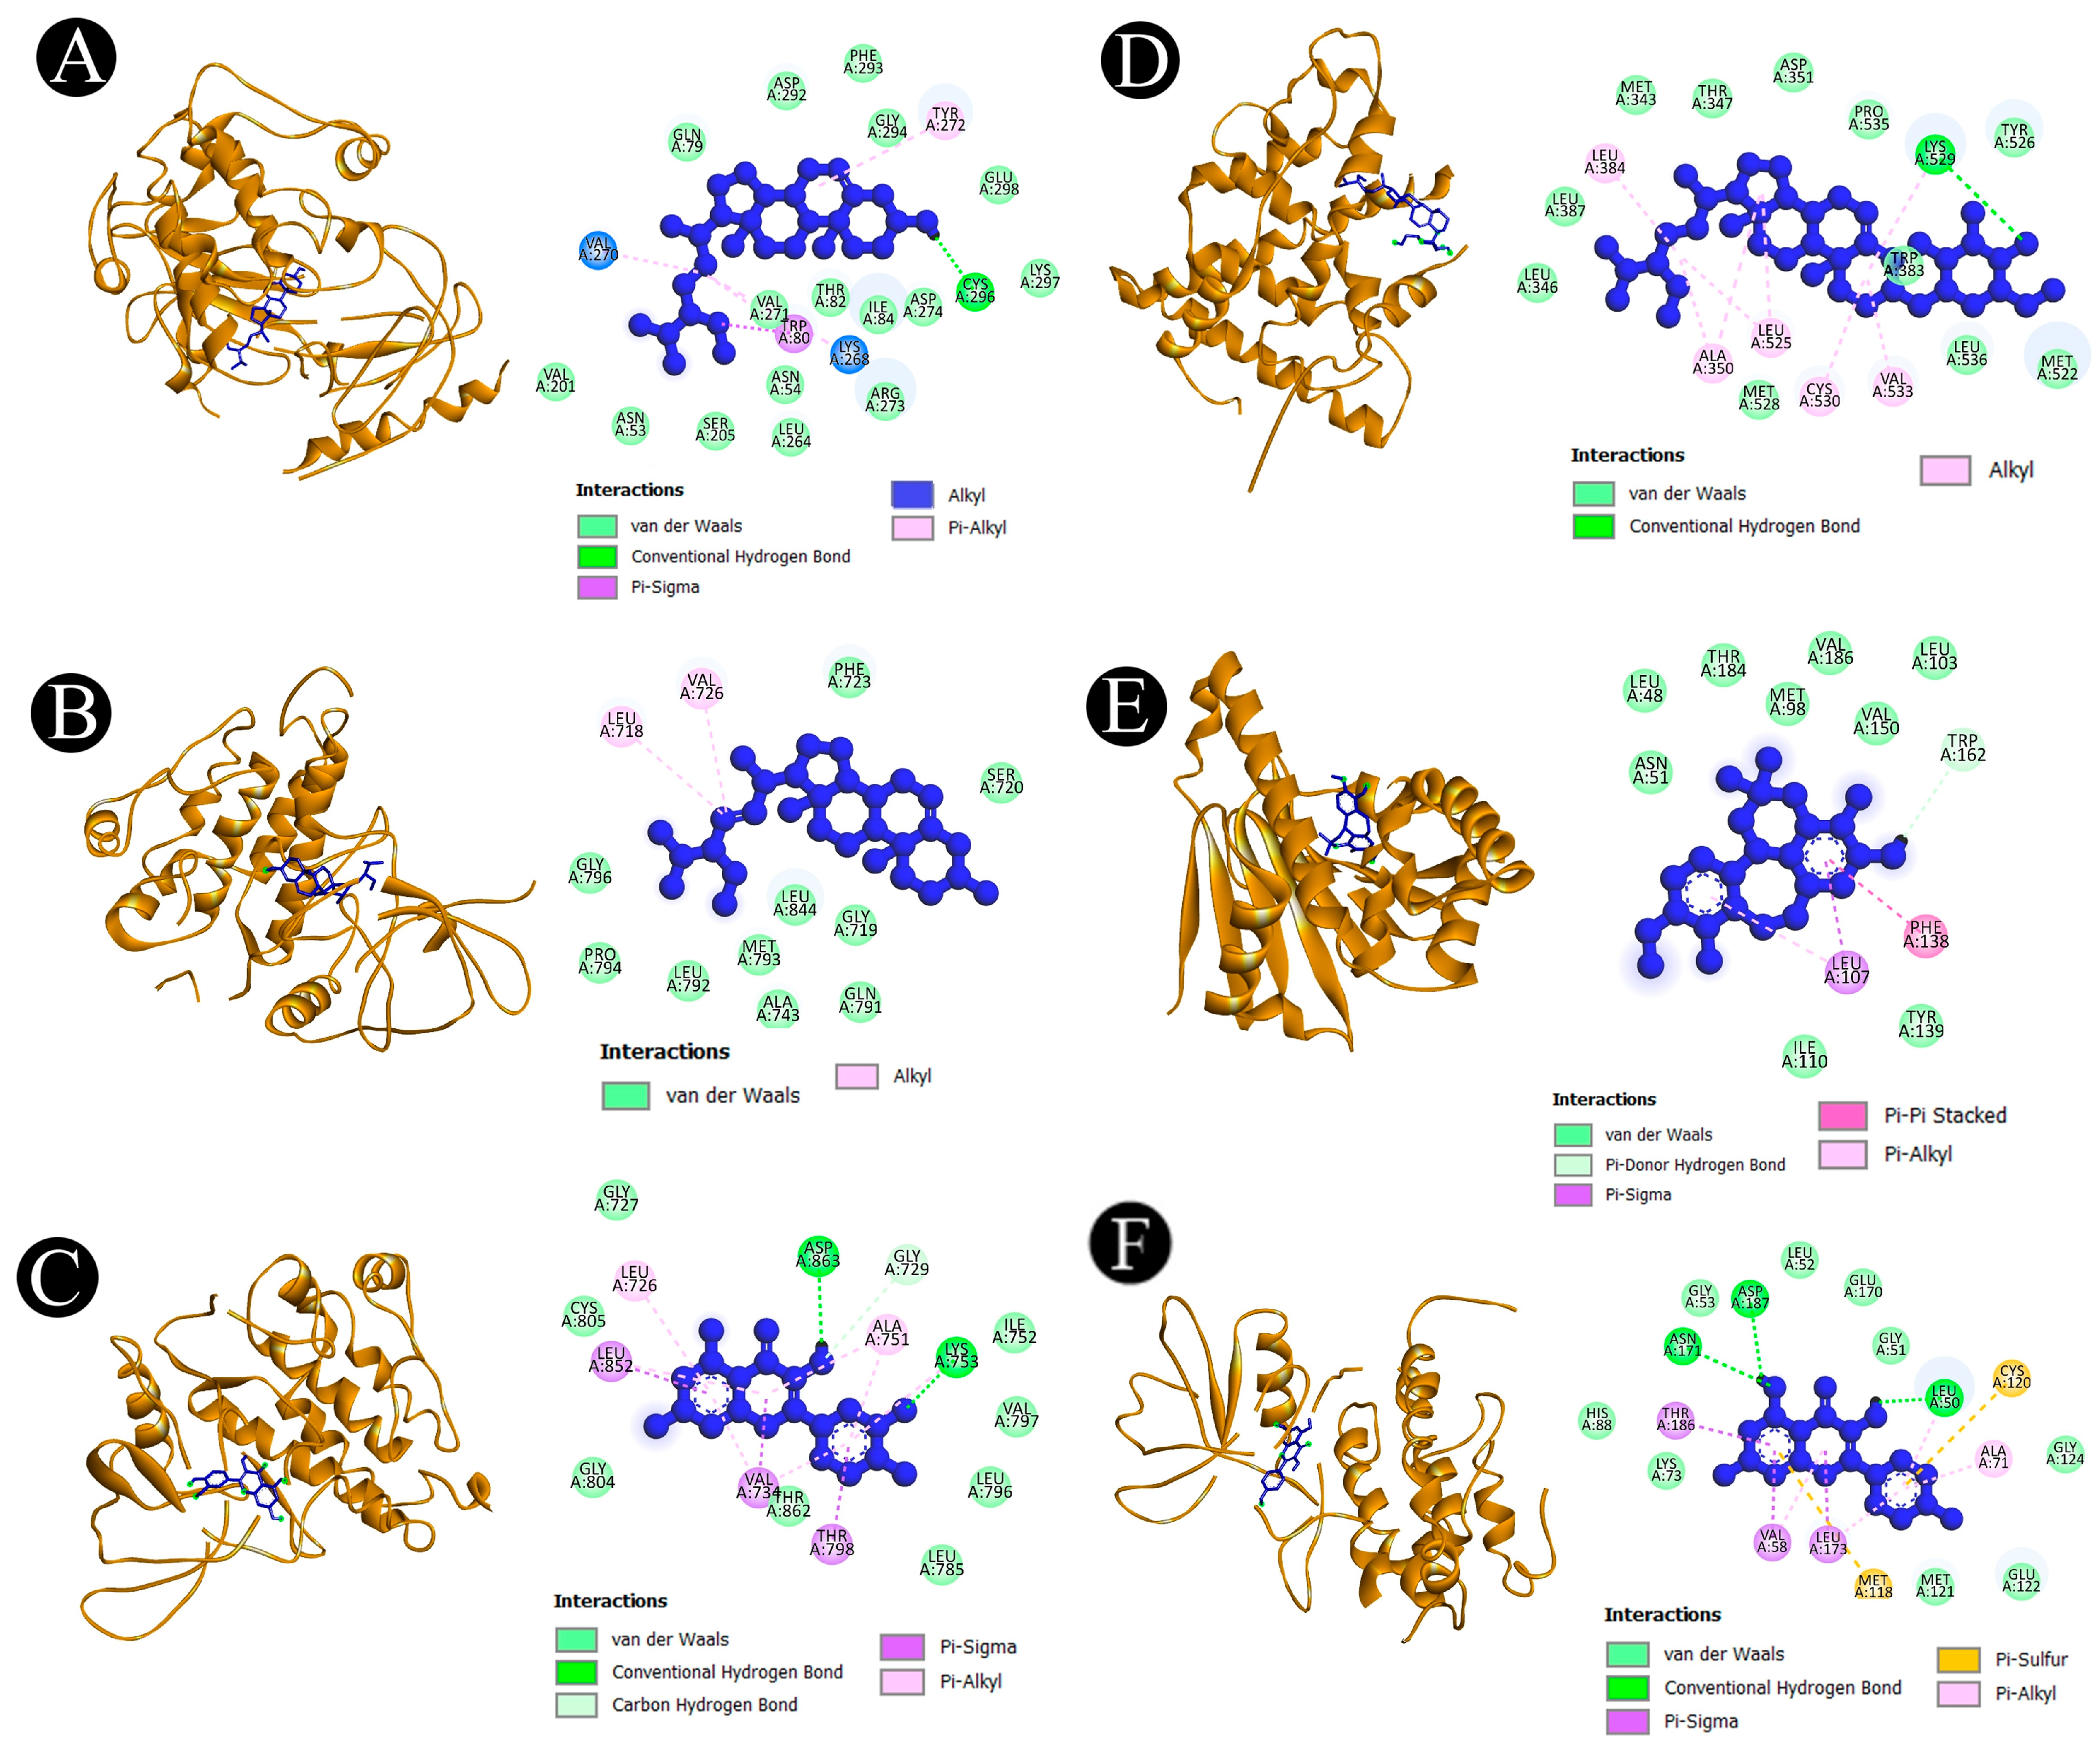

2.5. Binding Affinity and Molecular Interaction Analysis